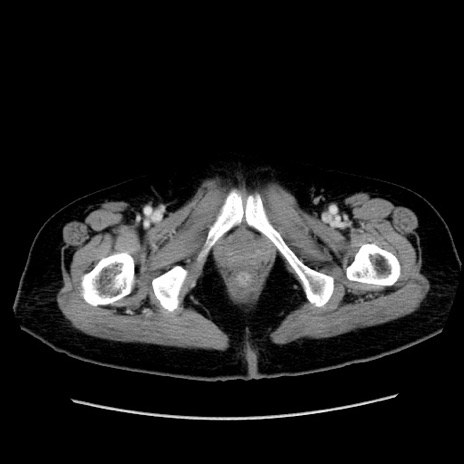

症例19(横断像)

【症例】80歳代女性

【主訴】下腹部痛

【現病歴】約8時間前より下腹部痛の出現あり、救急外来受診。

【既往歴】両側付属器切除

【身体所見】意識清明、下腹部正中に手術痕あり、その部位に一致して圧痛と反跳痛あり。腸蠕動音は亢進。

【データ】WBC 9300、CRP 0.15